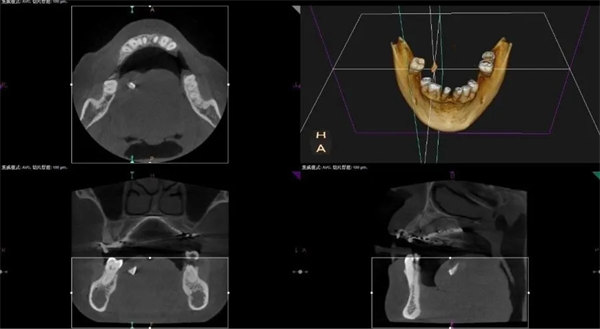

李少偉向科主任李偉匯報患者病情后,李偉再次仔細查體,認為患者舌背部有異物,立即安排口腔CBCT檢查,不出所料,影像學檢查結果顯示:舌體內存在異物,并且為患者受傷后脫落的牙齒殘片!明確病因,考慮到患者年長,為避免舟車勞頓,不容猶豫,李偉隨即決定加班為該患者進行手術。

術前CBCT檢查